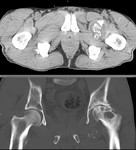

[画像診断]癌性リンパ管症のHRCT所見について 2010-09-22